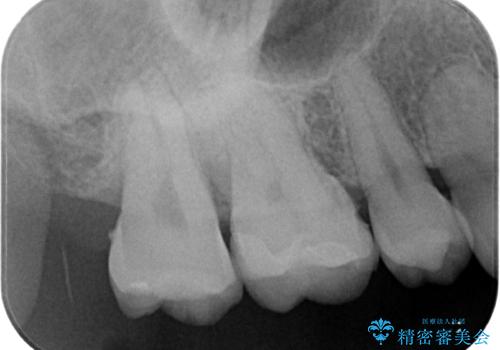

拡大鏡視野下でセラミックインレーに適した形に整えました。

歯と歯茎の間に圧排糸と言われる糸を入れてシリコーン印象材にて精密な型どりをしました。

セラミックインレーの装着時には、唾液の侵入を防ぐために、ラバーダム防湿を行いました。

見た目、機能面共に大変喜んでいただきました。